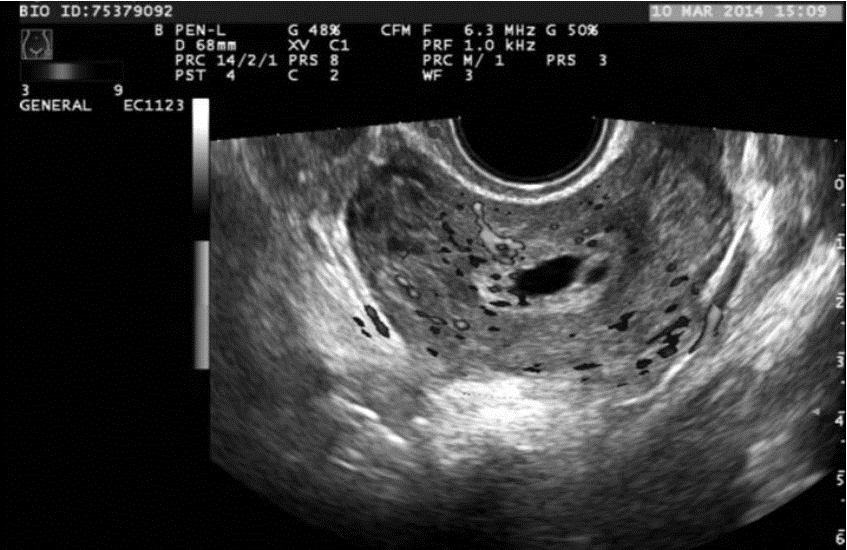

2 结果CDFI正确诊断切口妊娠和下段妊娠分别为17例、14例(图 1、图 2),CEUS正确诊断切口妊娠和下段妊娠分别为19例、20例(图 3、图 4)。CDFI、CEUS、CDFI及CEUS联合在切口妊娠与宫腔下段妊娠的鉴别诊断中差异具有统计学意义(P<0.05)。见表 1。

![]() |

| 图 3 CEUS显示子宫前峡部部分孕囊早期快速明显强化,增强时间为12s |

CEUS检查简便、快捷,不受角度及呼吸运动的影响,可清楚显示微血管和组织的血流灌注情况[8],可为切口妊娠的鉴别诊断提供更多的信息,从而提高切口妊娠的诊断准确度。本组CEUS诊断切口妊娠的敏感度90.5%,特异度83.3%,其敏感度与CDFI相似,而特异度较CDFI增高。笔者观察到宫腔下段妊娠的CEUS表现与切口妊娠不同,宫腔下段妊娠时CEUS可见子宫前峡部肌层与孕囊之间的弧形无强化间隙,且绒毛增强时间晚于切口妊娠组,本组20例宫腔下段妊娠绒毛开始增强时间18~38 s,(26.3±7.1)s,19例切口妊娠绒毛增强时间11~23 s,(16.1±4.3)s,两者差异具有统计学意义(P<0.01)。